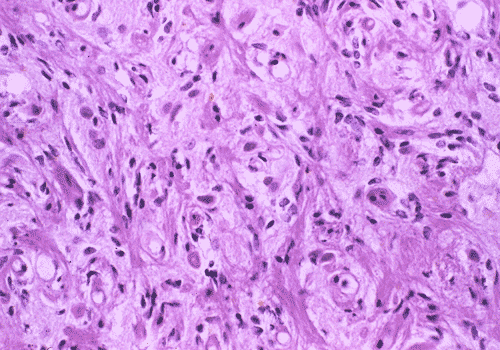

Histopathology: On histologic examination, the cortex lesion (C-L in Panel A) appear fibrous and vascular. It is well demarcated from the white matter (W in Panel A). The cortical lesion respects the grey-white junction and the interface is smooth. These features are better appreciated on Masson's trichrome stain. While one side of the gyrus is replaced by the lesion (C-L in Panel E), normal cortex is present on the other side of the gyrus (C-N in Panel E). White matter (W in Panel E) and the normal cortex (C-N in Panel E) carry a pink hue on Masson's trichrome.he fibrous lesion (C-L in Panel E) does not carry much of this pink hue.  The lesion essentially follow the shape of the gyrus with some cortical thickening (Panel F). On higher magnification, the cortical lesion is highly vascular (Panel B, C, and G). In between the fibrous vascular component, there are entrapped islands of cortical tissue (Panel D, H, and I ). There is a general lack of pleomorphism and mitotic activities in the lesion.

Histologically, the salient feature is a disorganized lesion featured by perivascular meningothelial cells intermingled with a fine, rich vascular network. Although each lesion is unique, increased cortical vascularity and perivascular cellular proliferation are constant findings. Irregularly branched blood vessels extending into the gray matter from the meningeal surface are surrounded by a concentric arrangement of proliferating spindle-formed cells .The overall structure can occur as nodules, whorls, or bands. Islands of cortical tissue with gliosis are often trapped within the lesion. The ratio between meningothelial component and vascular component varies substantially. There are lesions predominantly composed of vascular component or meningothelial component 3. A schwannian component can also occur. There are also cortical meningovascular fibroblastic proliferation and leptomeningeal calcifications that range from faint psammomatous calcification to dense osteoid. Residual neurons entrapped within the lesion may contain neurofibrillary tangles with ultrastructural and immunostaining properties identical to those seen in Alzheimer's disease but there is no deposition of amyloid Ab.